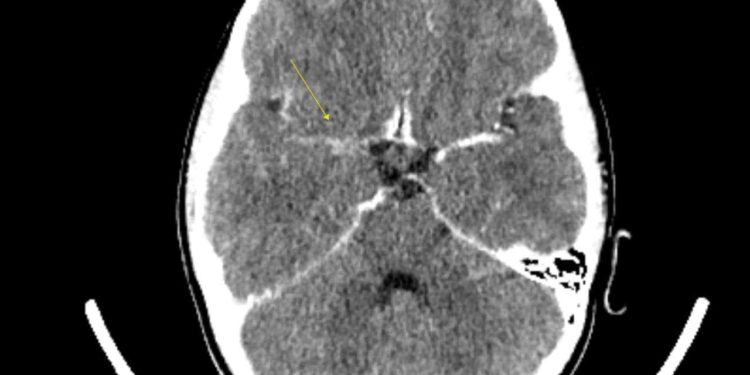

Під час КТ головного мозку з контрастуванням лікарі побачили судинні зміни, характерні для захворювання Моямоя. Хвороба моямоя (Moyamoya), що у перекладі з японської означає «клубок диму») – вкрай рідкісне захворювання. За статистикою зустрічається в середньому 5 випадків на десять тисяч людей і може проявлятися як в дитячому віці (пік виявлення 4 роки), так і в дорослому ( 30-40 років) віці. В основі захворювання лежить фіброзна проліферація стінок судин (їх звуження), і, як компенсація, утворення густої сітки колатералей.

«Для детальнішої візуалізації та передопераційної підготовки дитині зробили ангіографію в відділенні інтервенційної радіології, що підтвердило діагноз. Згодом дитині було проведено нейрохірургічне втручання – екстра-інтракраніальне шунтування», – пише Іван Міськів.